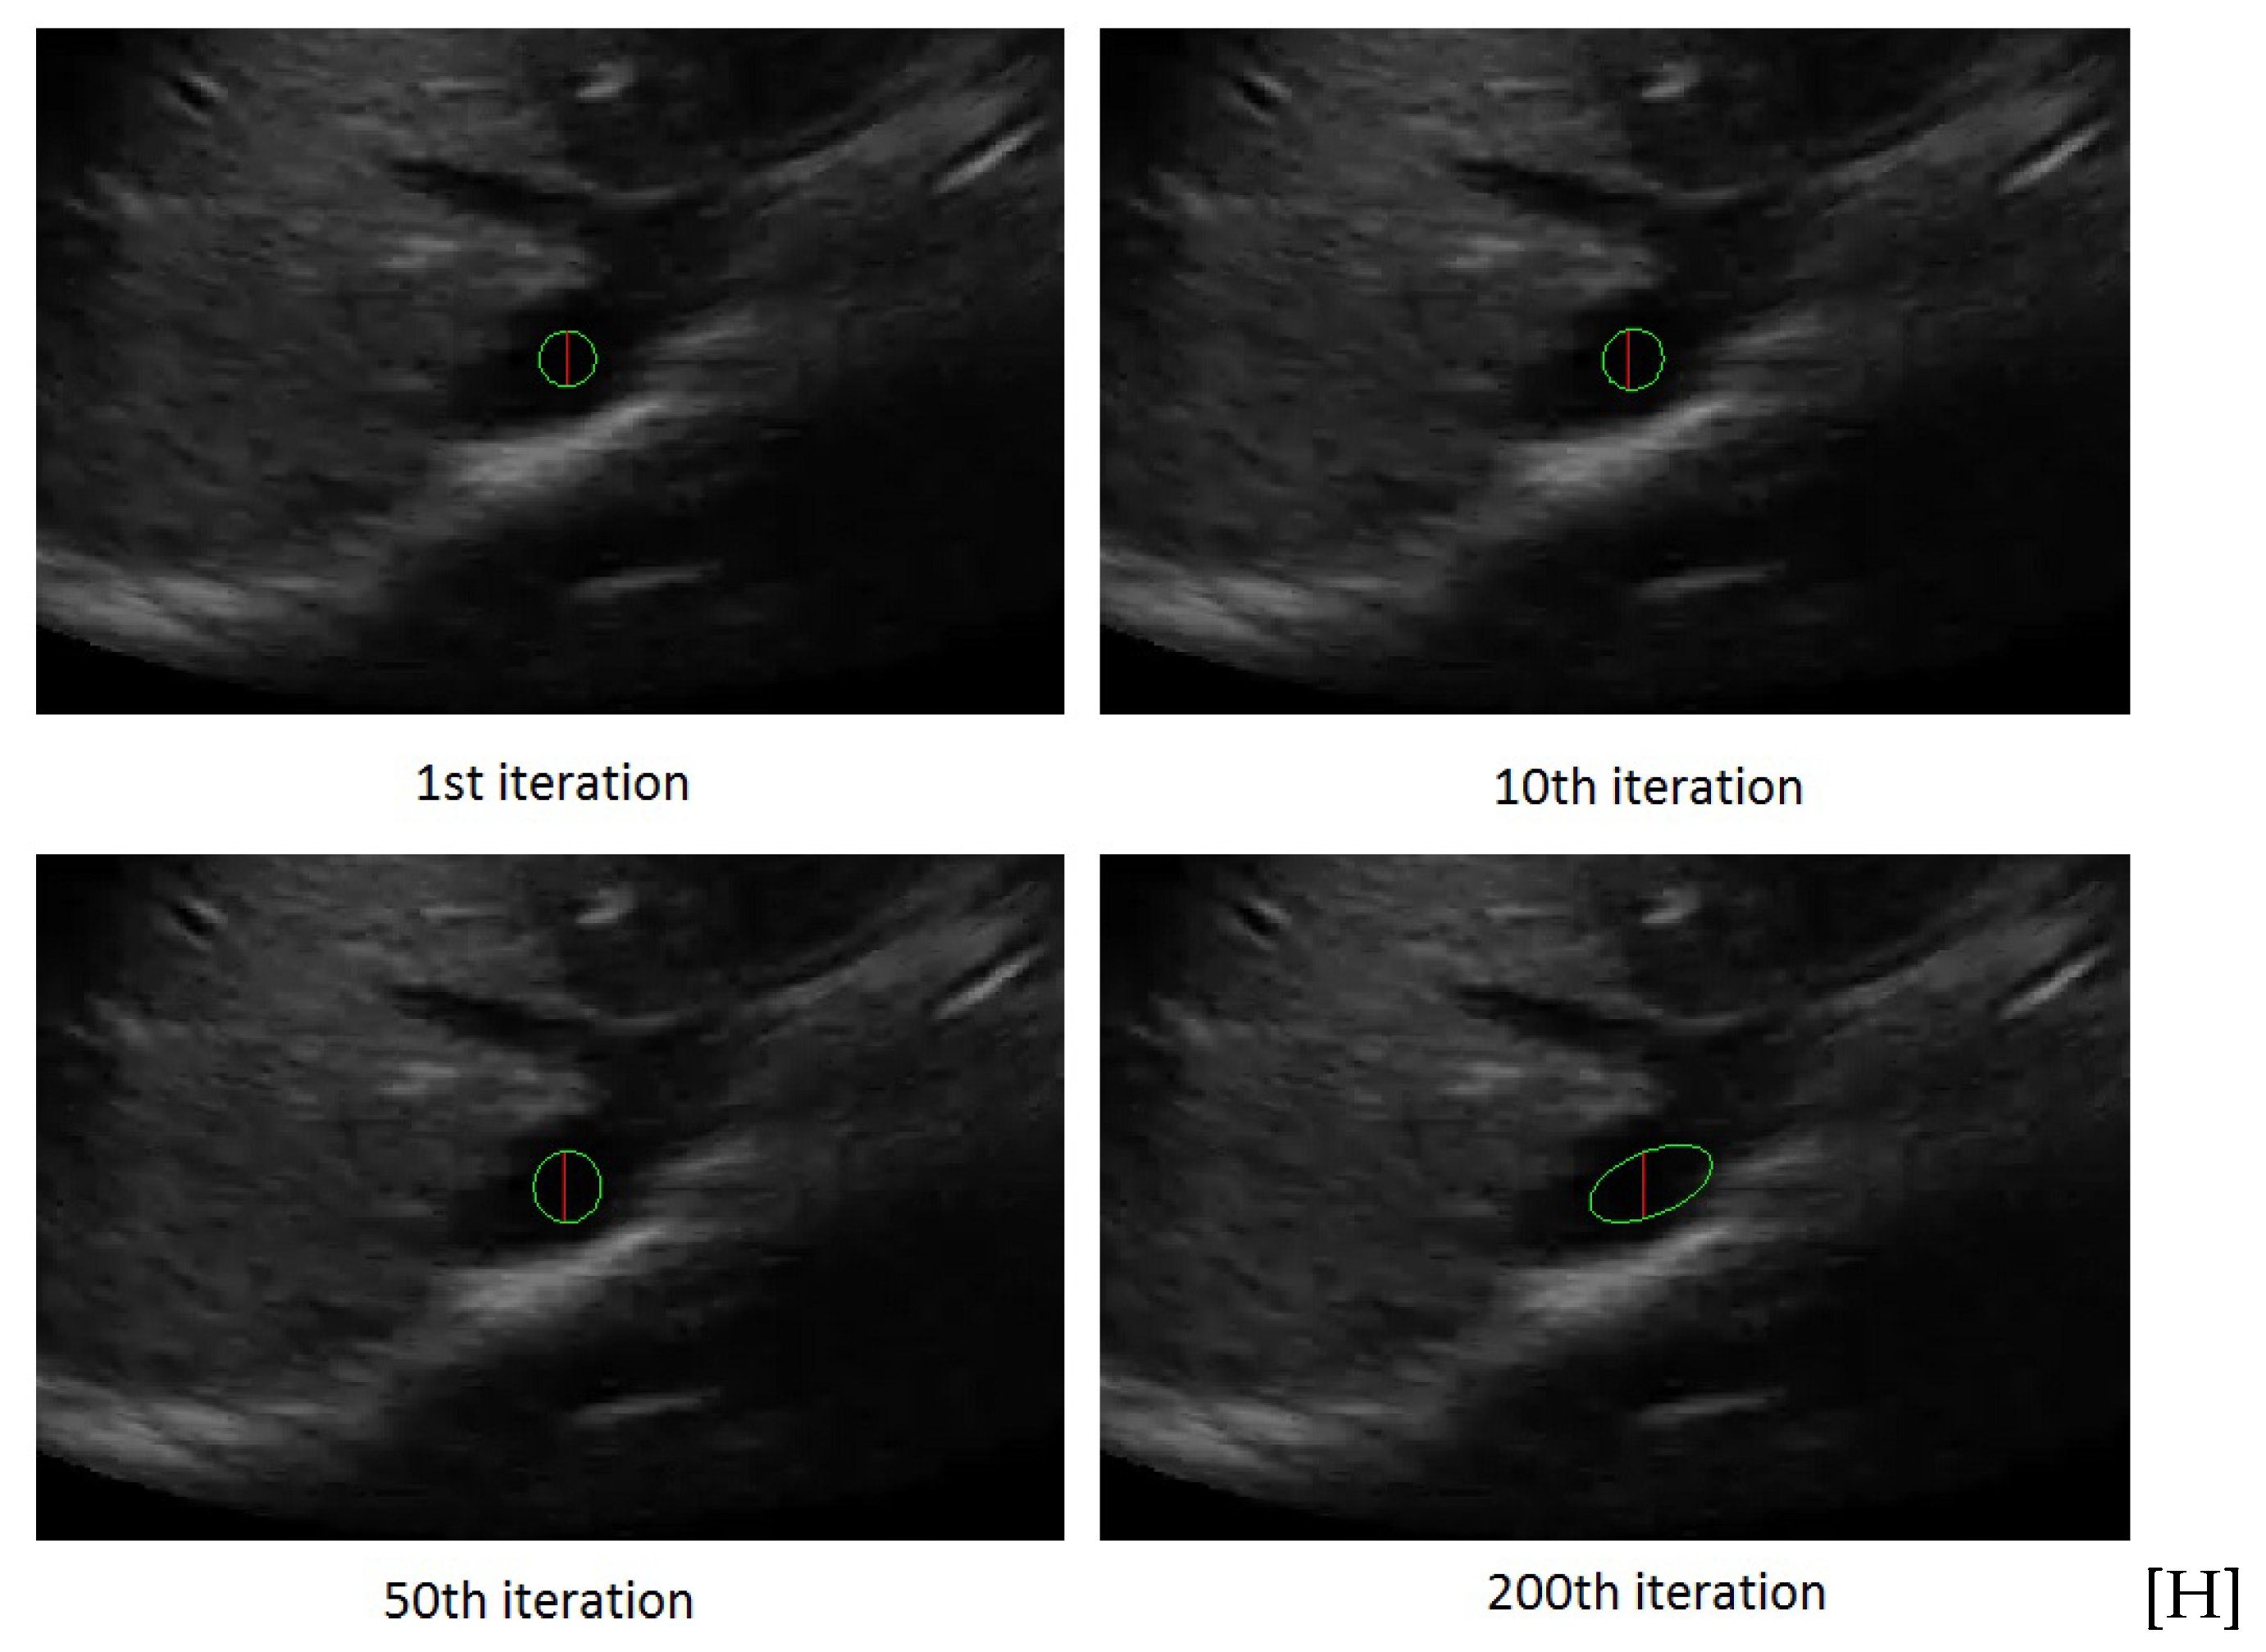

Figure 4 shows the rectangle evolution versus number of iterations for the IVC image as in Figure 2. By comparison of Figure 2 and Figure 4, one can see the active rectangle algorithm not only converges faster but also more accurately estimates the AP-diameter than the active ellipse algorithm.

Figure 4.

The rectangle evolution versus number of iterations.